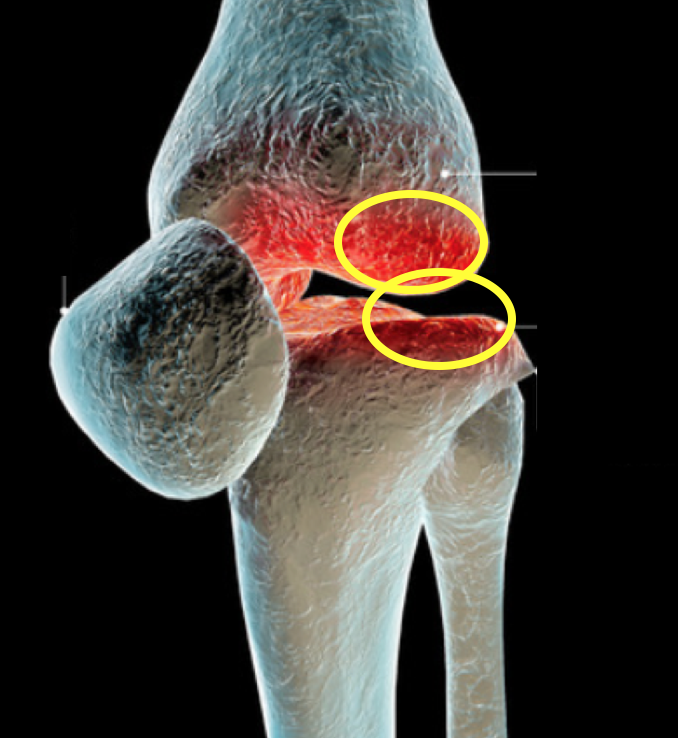

オレンジ色で塗りつぶされている部分

悪くなっている場所です。

一番最初の図で示している

①と③の部分が病変部です。